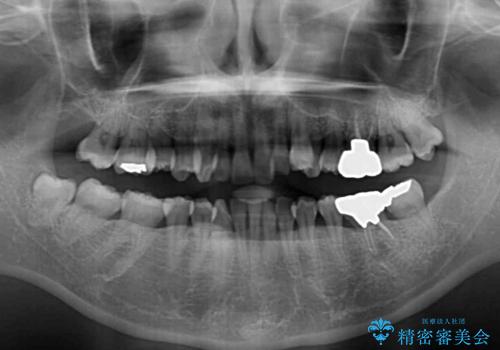

- 八重歯と正中のズレを気にして来院された患者様です。

上顎左側が八重歯になっており、上顎正中が左側にずれていました。

上顎左側の第一小臼歯を抜歯し、補助装置を用いて正中位置を改善しながら八重歯を解消していくこととしました。

下顎前歯が1本欠損していたため、上下正中の位置が合わせるという目標はなく、鼻筋に上顎正中を合わせていくように移動を行いました。